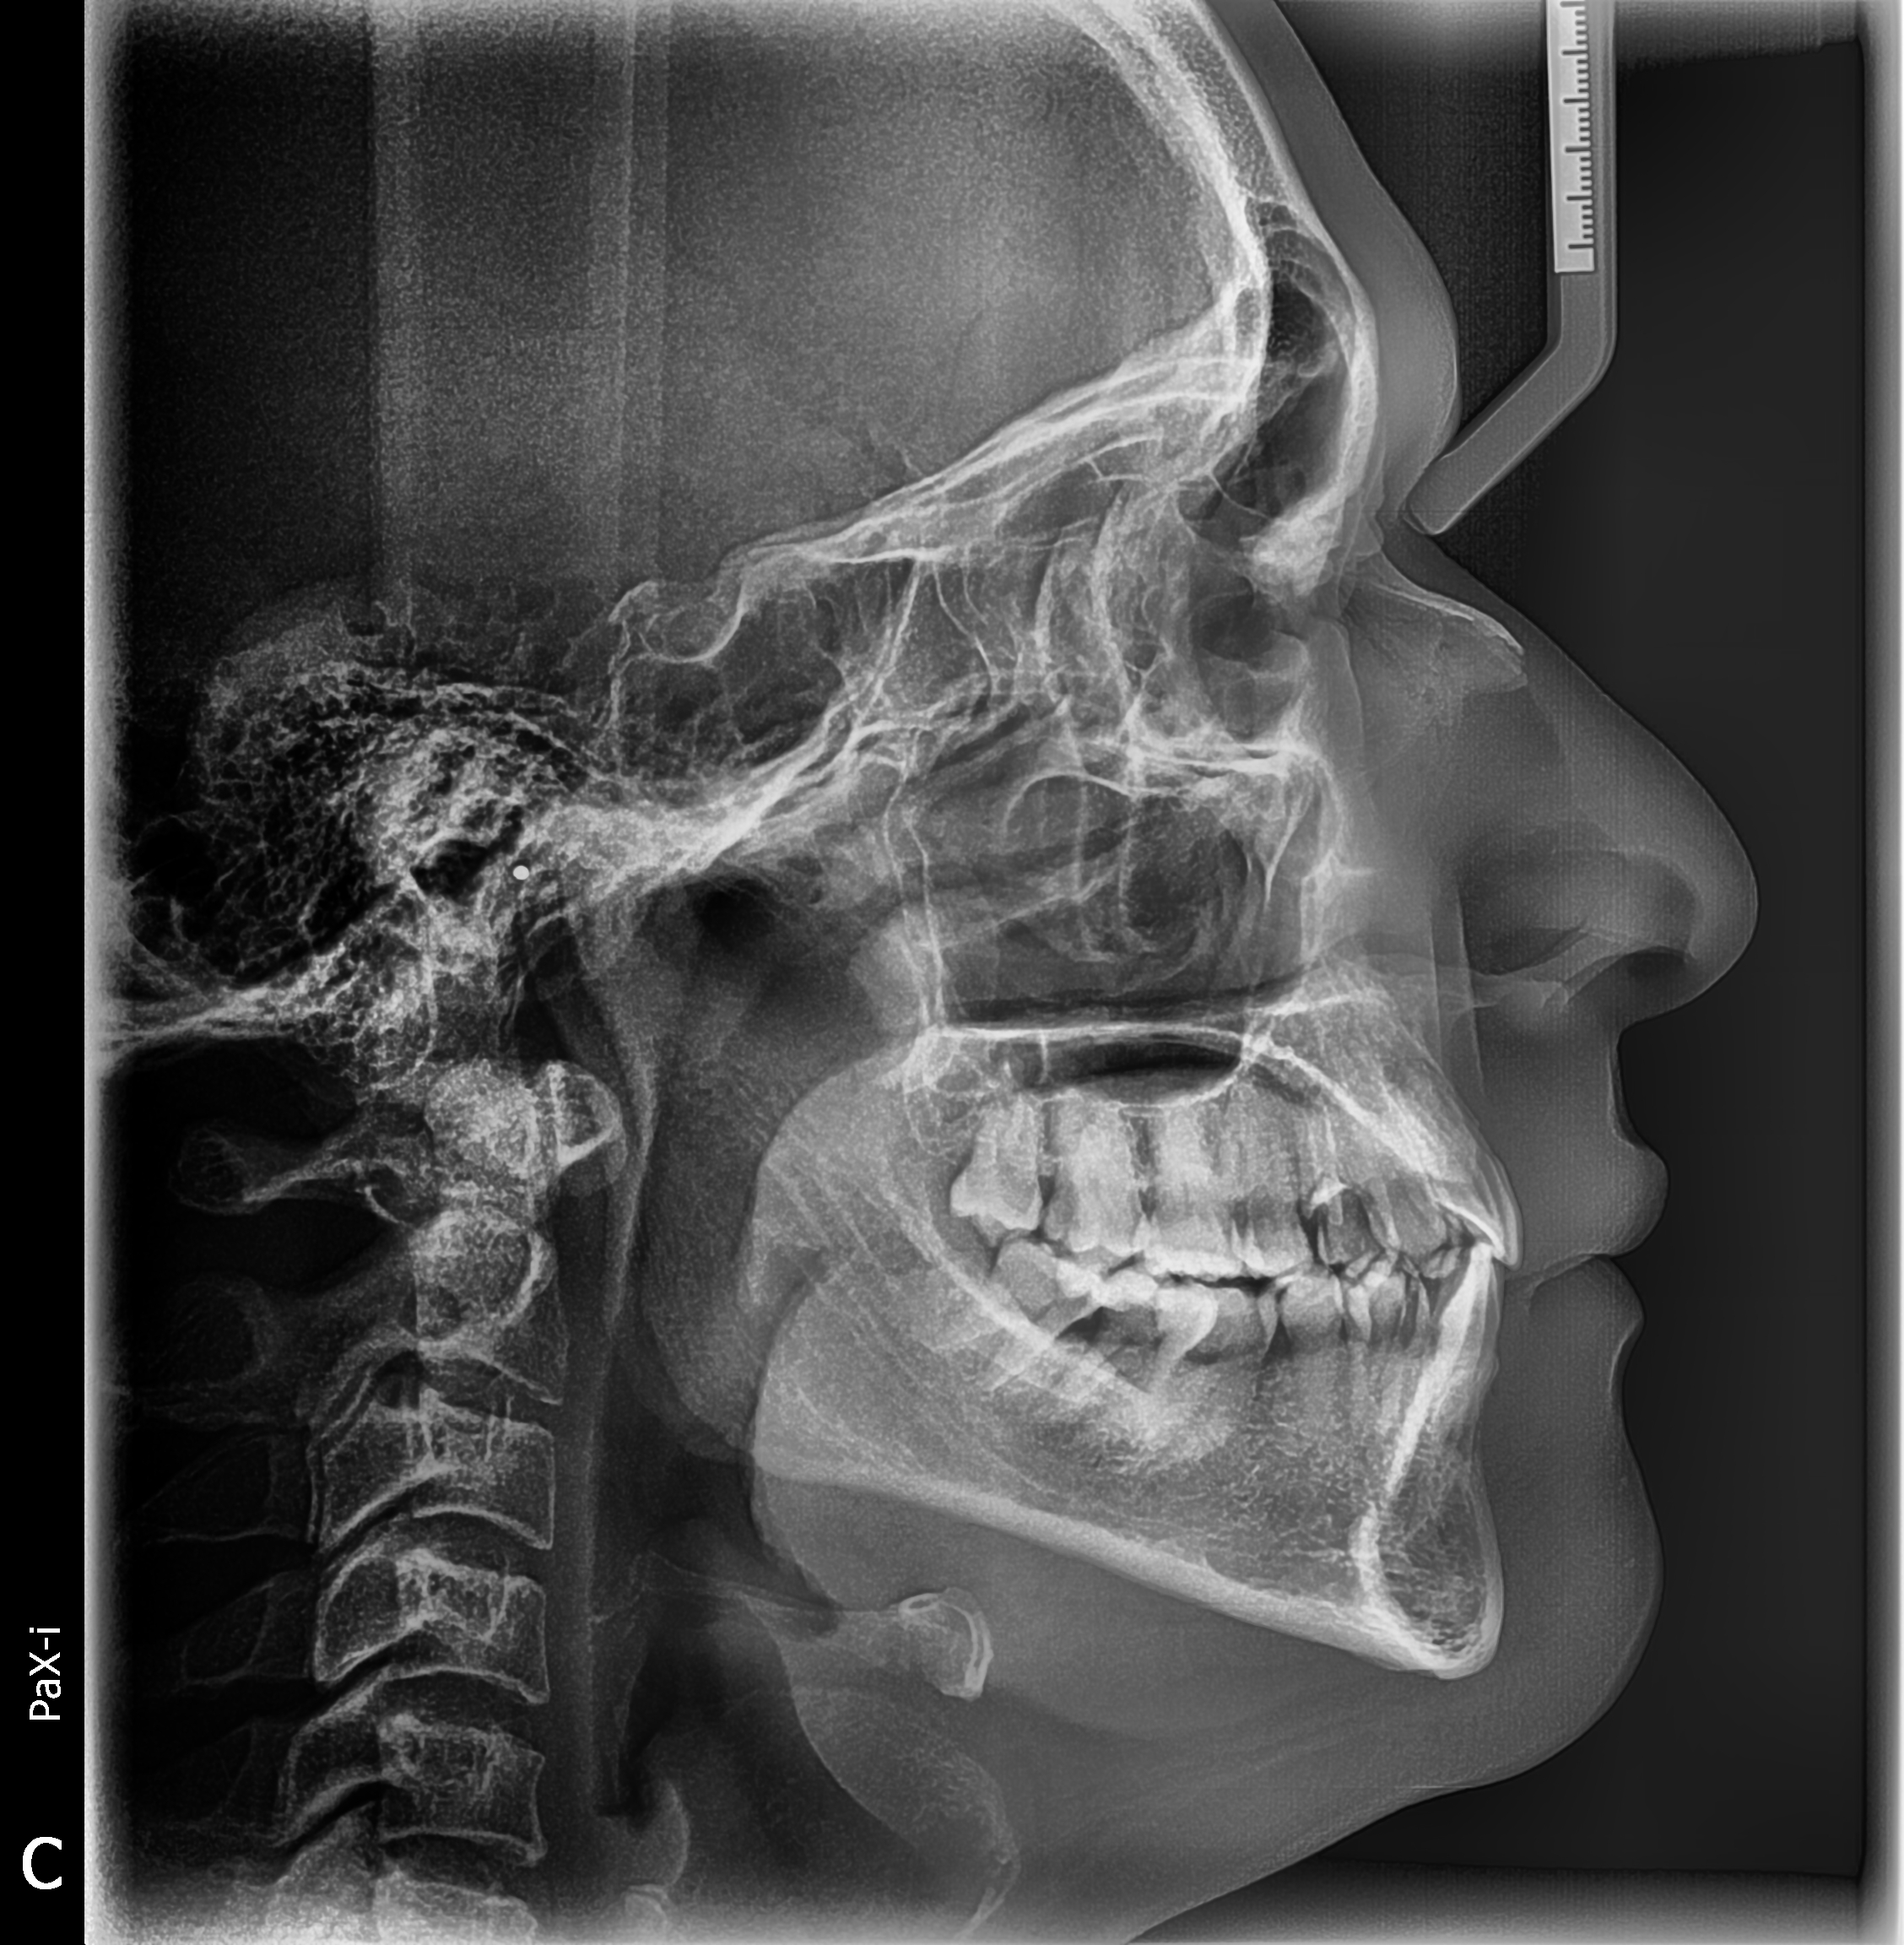

Gracias al Dr. WILMER CERNA, por seguir confiando en nosotros y adquirir su nuevo equipo. Centro ubicado en Carabayllo, instalación de equipo PaX-i SC (Panorámico/Cefalometrico) de la marca VATECH.